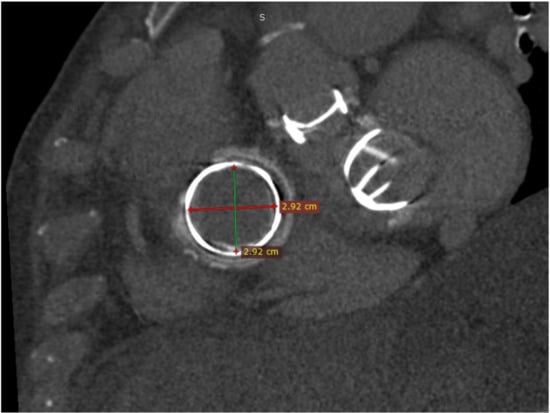

The right lung was retracted to expose the pericardium and 2 Prolene 3.0 (Ethicon, Somerville, NJ, USA) purse-string sutures reinforced with pledges were placed in the lateral wall of the right atrium. A bolus of 5000 IU of heparin was administered intravenously prior to puncturing the right atrium in the middle of the purse-string sutures. The interventional cardiologist was guided by TEE during the whole procedure. The dysfunctional tricuspid valve was accessed with a soft J-guidewire inserted through the puncture and advanced to the right ventricle. Afterwards, a 7F sheath with a pigtail catheter was mounted with subsequent removal of the guidewire. A Confida (Medtronic, Minneapolis, MN, USA) stiff wire with a preshaped loop was inserted through the pigtail to the apex of the right ventricle (Figure 3) to ensure stability for transcatheter valve crossing from the right atrium to the right ventricle.

Figure 3. Fluoroscopic image showing the mechanical mitral and aortic prostheses, the tricuspid bioprosthesis, prior pacing leads and the stiff wire.